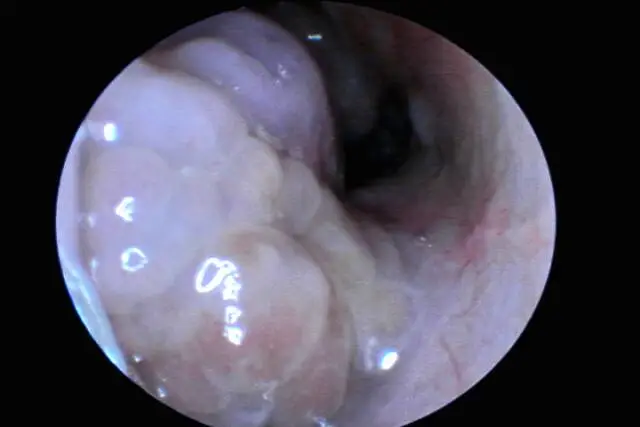

鼻息肉在临床上被定义为鼻腔或鼻窦黏膜上突出的增生性组织团块,其发病群体以成年人为主,儿童与老年人患病概率相对较低。鼻息肉不仅会损害全身健康,更会直接影响鼻部生理功能,引发一系列针对性问题,以下为详细说明:

鼻息肉会直接堵塞鼻腔通道,且鼻塞程度与息肉体积正相关——息肉越大,堵塞越严重,从单侧间歇性鼻塞逐渐发展为双侧持续性鼻塞。鼻腔通气受阻后,内外气体交换不畅,会导致鼻腔黏膜长期处于潮湿、缺氧环境,反复受到分泌物刺激,进而诱发或加重鼻炎鼻窦炎等继发性鼻部疾病,形成“堵塞→炎症→息肉增大”的恶性循环。

正常嗅觉的产生依赖气流携带气味分子到达鼻腔顶部的嗅觉区域,而鼻息肉引发的严重鼻塞,会阻碍气味分子与嗅觉神经末梢的接触——轻则仅有部分气体能到达嗅觉区,导致嗅觉灵敏度下降,对气味感知模糊;若鼻塞持续加重或息肉直接压迫、损伤嗅觉神经,会导致患者完全无法闻到气味,最终发展为永久性嗅觉丧失。

鼻息肉作为鼻腔内的异常增生组织团块,当体积较大或呈多发性生长时,会逐渐向外挤压鼻腔及鼻窦周围组织,导致鼻部外观出现肿大、变形。肿大程度因人而异,主要取决于息肉的大小、数量及生长位置:轻症者可能仅表现为鼻部轻微隆起,重症者则可能出现鼻梁变宽、鼻翼肥大等明显形态改变,影响面部美观。